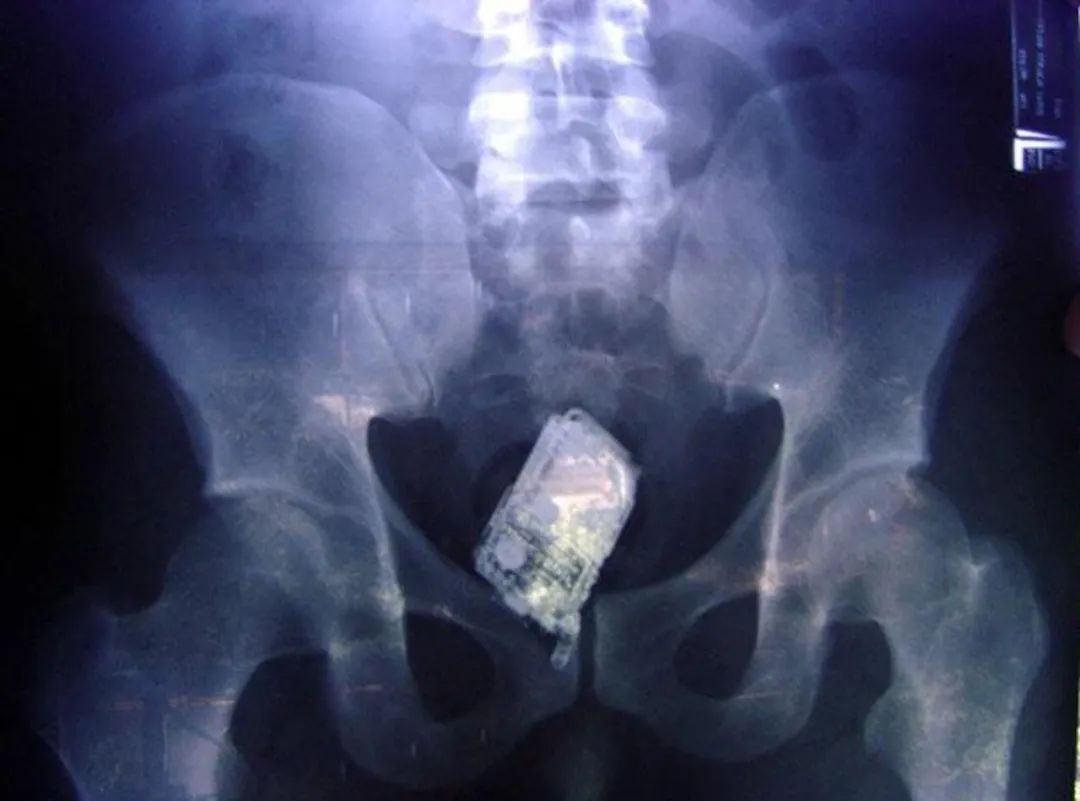

12 一位律师和他会震动的手机的故事

据乔治亚洲的一名律师亲口描述,他在带着手机洗澡的时候(防水功能挺好),不小心在一块瓷砖上滑倒了,结果好巧不巧就坐到了他正在震响的手机上面。“手机就是这么进入我体内的。”

医生们花了不小的功夫艰难地把手机取了出来,因为间断的三次响铃及震动打断了手术进程。这位先生刚离开,手术室里就忍不住爆发出欢快的笑声——大概是因为他的手机铃声太有趣了。

嗯,一定是这样的。